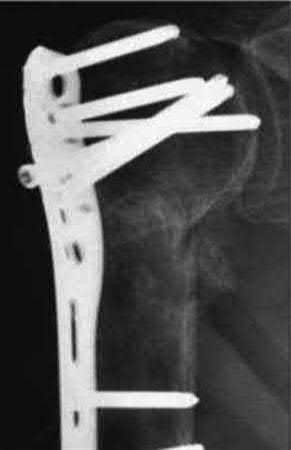

A 64-year-old woman is thrown off a horse, sustaining the injury shown in Figures A and B. She undergoes surgical fixation as seen in Figures C through E. What is the most commonly reported complication of this procedure?

1) Axillary nerve injury

The patient in the scenario has a 2-part proximal humerus fracture treated with a locking plate as seen in Figures A-E. The most common complication with the use of this implant is screw penetration. The terms screw cut out and penetration are often used interchangeably in the literature with cut out appearing more frequently in reports regarding intertrochanteric fractures.

Owsley et al retrospectively reviewed 53 proximal humerus fractures treated with locking plates and the same post-operative protocol. The most common complication was screw cut out or penetration, followed by varus displacement. They concluded that 3 and 4-part fractures in patients over 60 years have a higher incidence of failure.

Agudelo et al retrospectively reviewed 153 patients at a level-one trauma center treated with proximal humerus locking plates, investigating modes of failure for the implant. They determined that varus malreduction (head-shaft angle